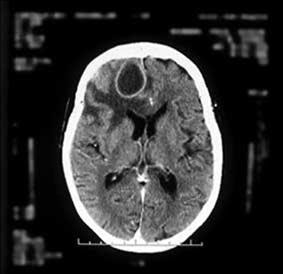

Résumé Face à un tableau de méningite ou méningoencéphalite aseptique , trois groupes de pathologies sont à évoquer: (i) les maladies systémiques susceptibles de s’accompagner de méningites, qui sont principalement la sarcoïdose, la maladie de Behcet, le syndrome de Sjögren, le lupus et la granulomatose de Wegener. On peut réaliser une ponction lombaire (rachicentèse) pour prélever un échantillon de liquide céphalorachidien. Une tomodensitométrie (TDM) ou une imagerie par résonance magnétique (IRM) est réalisée en premier lieu si les médecins suspectent qu’une augmentation de la pression intracrânienne ou qu’un kyste cérébral ou une autre masse dans le cerveau sont en cause.